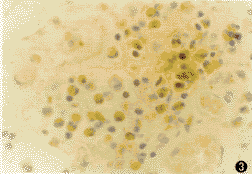

嗜酸粒细胞主要分布于鼻息肉粘膜下固有层。chromotrope 2R染色可特异性地将嗜酸粒细胞的胞浆染成粉红色,可准确辨别嗜酸粒细胞(图1,2),显示组织中嗜酸粒细胞的浸润状况。对照组10例中鼻甲组织中有8例存在嗜酸粒细胞浸润,其中有4例可见散在EG2阳性嗜酸粒细胞。未治组中变应性患者和非变应性患者在EG2阳性细胞密度、chromotrope 2R阳性细胞密度和嗜酸粒细胞活化比例(EG2阳性细胞个数/chromotrope 2R阳性细胞个数)比较差异均未见显著性(P>0.05)。激素治疗组EG2阳性细胞和chromotrope 2R阳性细胞的密度均较未治组减少(图3,4),但差异未达显著性水平(P>0.05)。而激素治疗组嗜酸粒细胞活化比例则明显低于未治组,差异有非常显著性(P<0.01,表1)。

图3 未治组鼻肉中较多EG2+细胞浸润。ABC免疫组化染色×200

图4 治疗组鼻息肉中EG2+细胞减少。ABC免疫组化染色×132